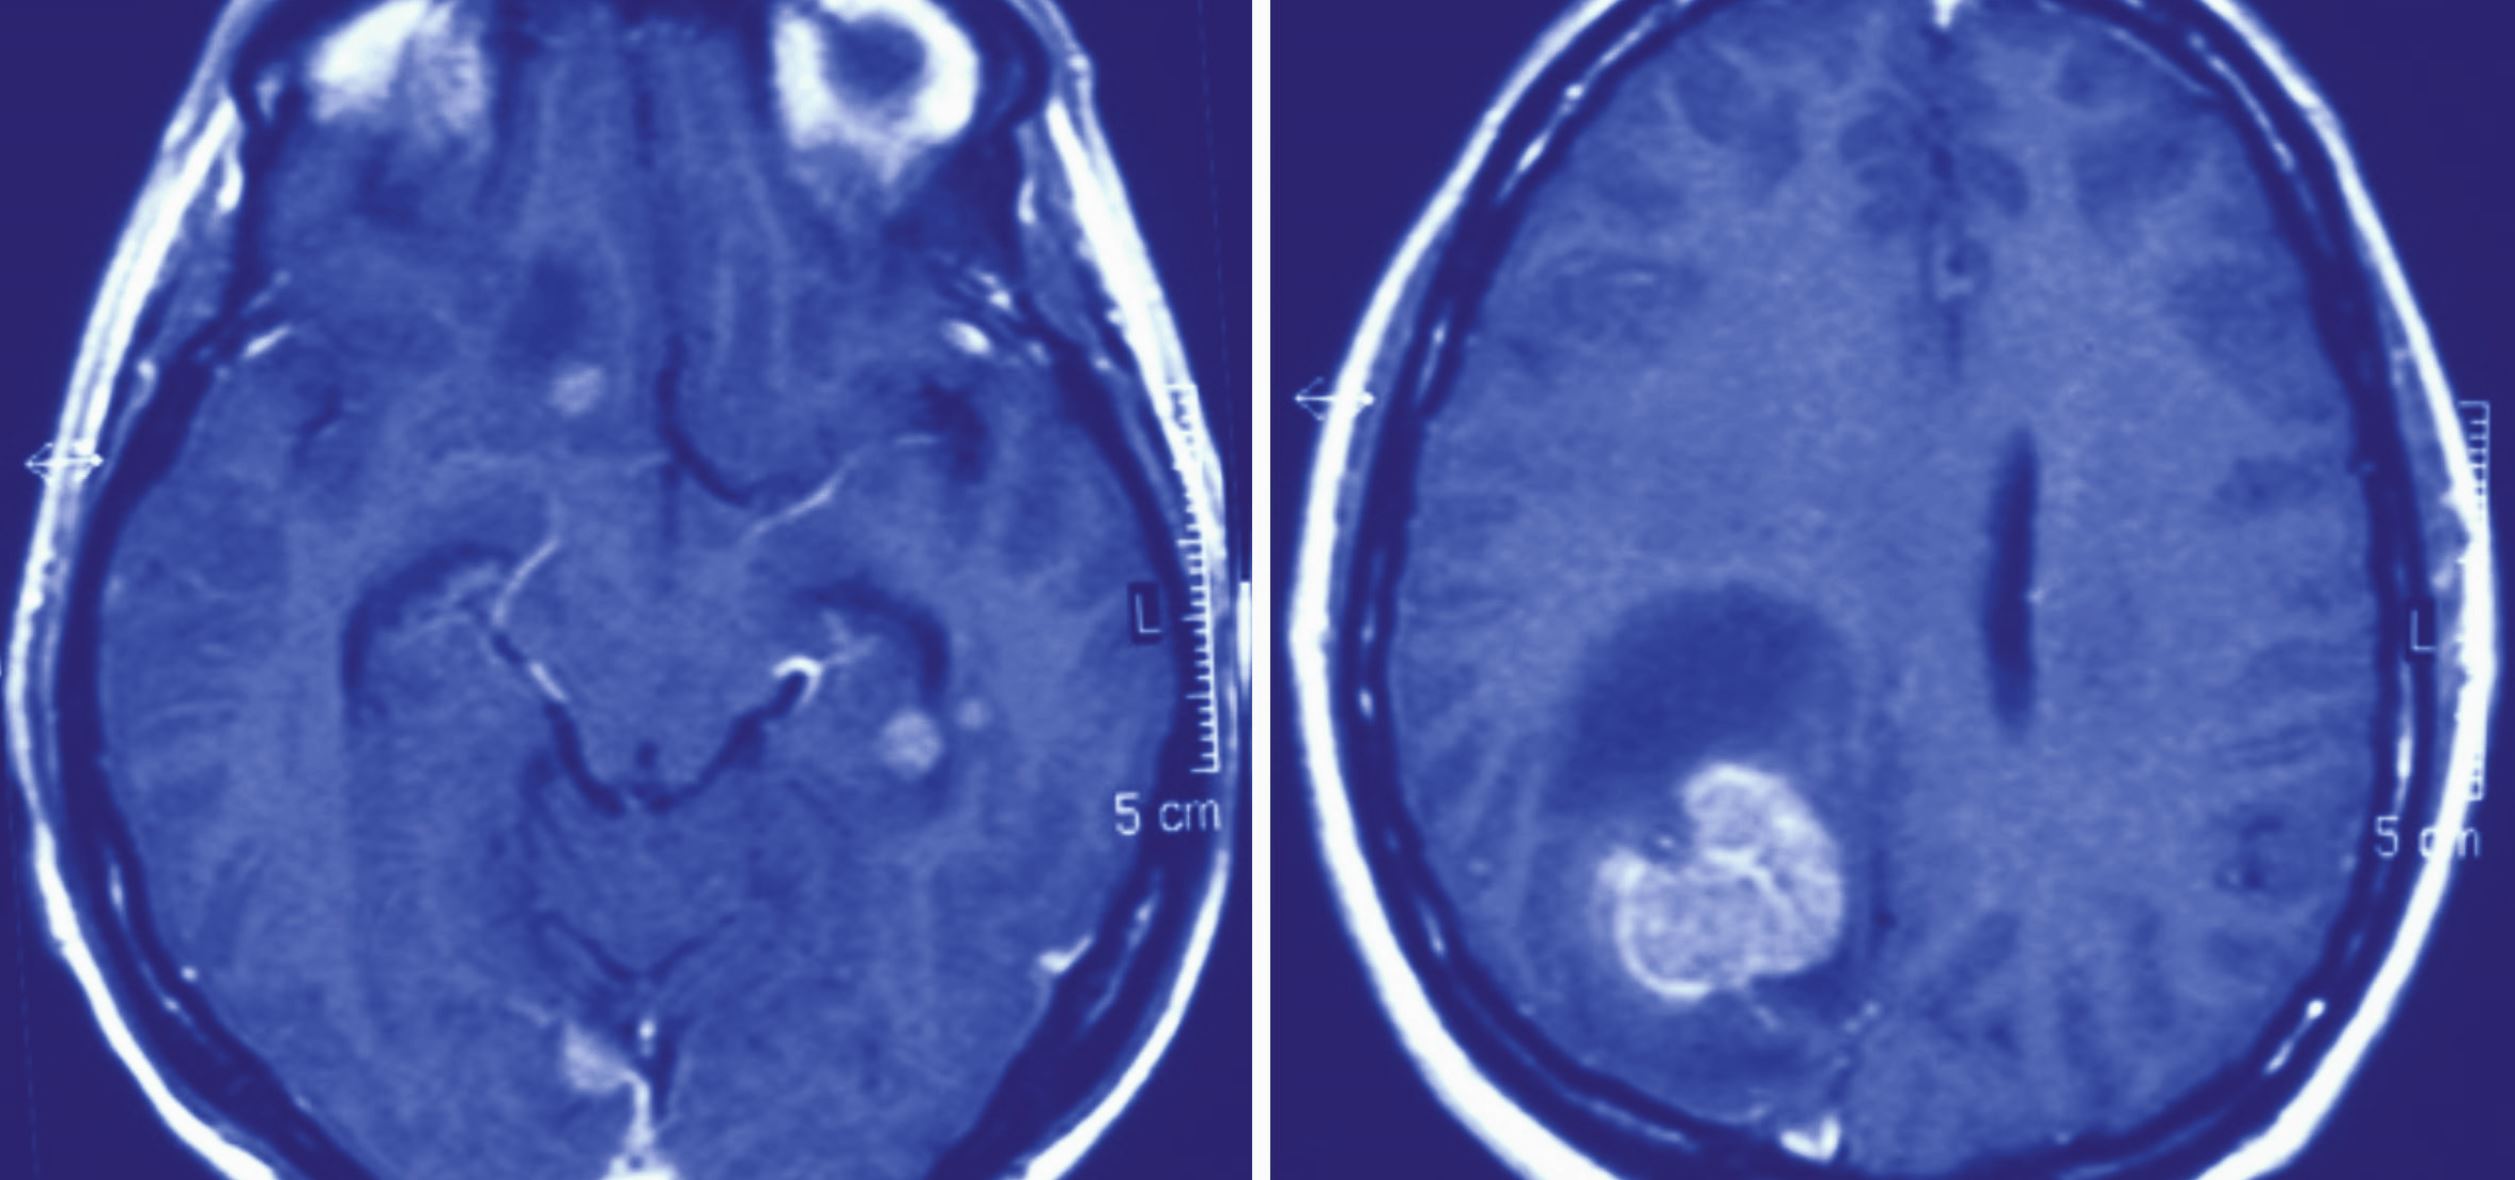

Hirnmetastasen sind die häufigsten Hirntumoren im Erwachsenenalter. Die Standardtherapie umfasst neurochirurgische und strahlentherapeutische Ansätze sowie medikamentöse Therapien in Abstimmung auf den Primarius. Dabei gewinnen biologische und pharmakologische Aspekte, die spezifisch für das ZNS sind, zunehmend an Bedeutung. Dieser Artikel gibt einen Überblick über den aktuellen Therapiestandard.

Hirnmetastase eines nichtkleinzelligen Lungenkarzinoms frontal rechts/© Diehl, C., Combs, S.E. / all rights reserved Springer Medizin Verlag GmbH, Berlin/© amyrxa / stock.adobe.com